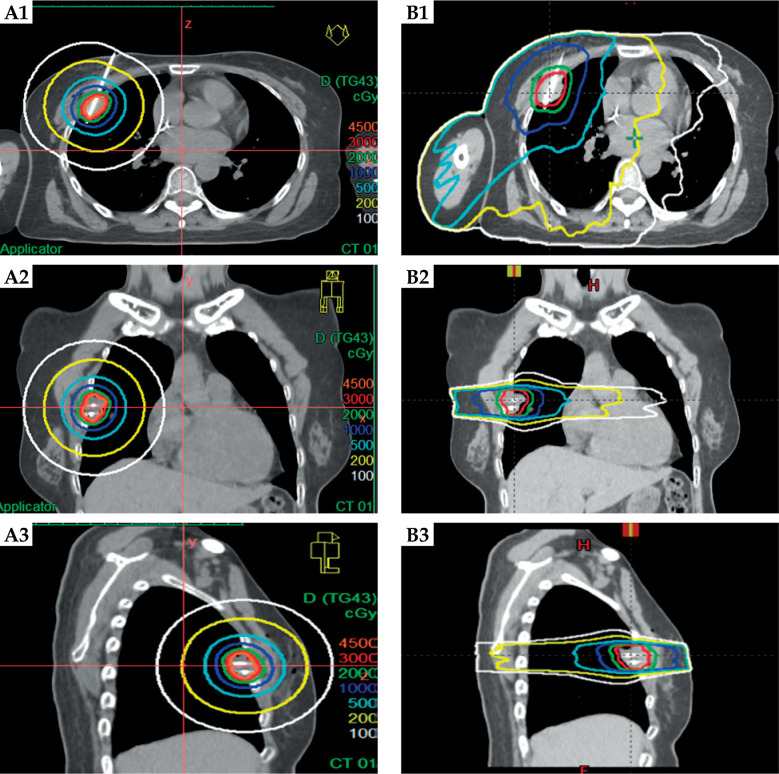

Material and methods: This single-centre retrospective cohort study involved 21 patients with pleural/chest wall malignant tumours treated between January 2024 and January 2025. All patients underwent HDR ISBT (30 Gy in a single fraction). Treatment included CT-guided needle implantation, three-dimensional dose optimisation (Oncentra system), and adherence to Radiation Therapy Oncology Group dose constraints for organs at risk (OARs). Efficacy endpoints included objective response (Response Evaluation Criteria in Solid Tumours v1.1), pain relief (Numerical Rating Scale), and dosimetric comparison with virtual stereotactic body radiotherapy. Safety was assessed using the Radiation Therapy Oncology Group/European Organisation for Research and Treatment of Cancer toxicity criteria.

Results: The median follow-up duration was 7.48 months. The objective response rate (complete response + partial response) was 76.19%, with 28.57% achieving a complete response and 47.62% achieving a partial response. Pain relief was achieved in 87.5% of patients with pretreatment pain, with numerical rating scale scores decreasing from moderate to severe (median, 6) to mild (median, 3) at 1 month. No ≥ grade II complications (e.g. bronchopleural fistula, pneumothorax) occurred; only four patients experienced minor subcutaneous haemorrhage/emphysema. Dosimetric analysis showed a significantly higher target mean dose with ISBT than with stereotactic body radiotherapy (p < 0.001), while OARs doses (e.g. lungs, heart, spinal cord) remained within Radiation Therapy Oncology Group limits. Rib and chest wall dose exceedances were rare and clinically insignificant.

Conclusions: Computed tomography-guided 192Ir HDR ISBT offers safe, effective local control and rapid pain relief for pleural/chest wall tumours, demonstrating superior dosimetric conformity and lower toxicity to OARs. This minimally invasive approach is a viable option for patients unsuitable for surgery or external beam radiotherapy.